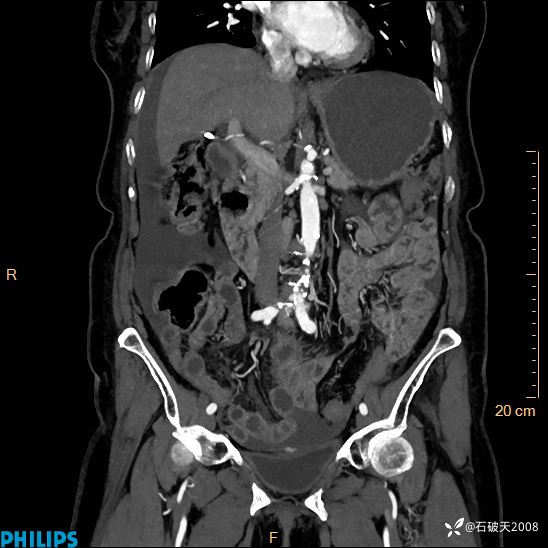

平扫